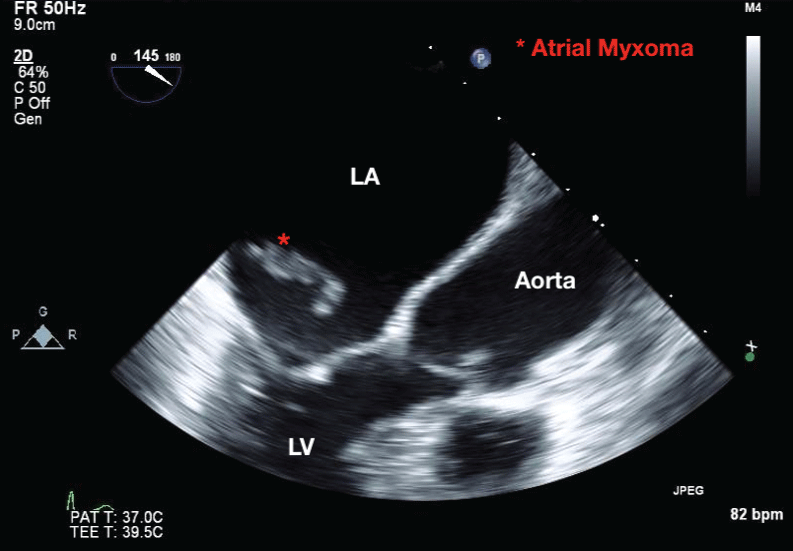

On admission, the patient was asymptomatic and vital signs revealed blood pressure of 135/80 mmHg, heart rate of 87 bpm, and oxygen saturation of 98% on room air. Laboratory analysis was unremarkable, except for hemoglobin level of 98 g/L. Electrocardiogram showed normal sinus rhythm. TTE confirmed a 4 × 1 cm mobile echo-dense mass arising from interatrial septum (LA side), and prolapsing through the mitral valve during diastole (Figure 1a and Figure 1b). The left ventricular ejection fraction (67%) and valvular function were normal. Non-stress test confirmed a reassuring fetal status in a cephalic presentation. Following discussion between cardiologists, cardiothoracic surgeons, obstetricians and anaesthetist, consensus decision was made to perform caesarean section first, with a view to proceed with cardiac surgery the following day after stabilizing the patient. She underwent an uncomplicated caesarean section with tubal ligation under general anesthesia, combined with Transesophageal Echocardiography (TEE) (Figure 2), and gave birth to a male infant, weighing 3.670 g with Apgar scores of 8 and 9 at 1 and 5 minutes, respectively. Hemi-sternotomy was employed and 30,000 Units of IV heparin was administered prior to her heart put on Cardiopulmonary Bypass (CPB) machine. A left atrial mass was resected from the interatrial septum and the defect in the septum was approximated with a patch. The CPB time was 59 minutes. The histology was consistent with a benign cardiac myxoma (Figure 3). She had an unremarkable recovery, and was discharged on day five post cardiac surgery. Short and long-term follow-ups are expected, as per cardiology clinic protocol.

Figure 2: Transesophageal echocardiography demonstrating an atrial myxoma in the left atrium during systole (red asterisk). View Figure 2